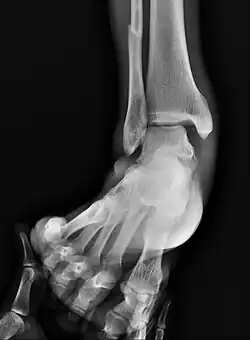

Fracture of both sides of the ankle with dislocation as seen on anteroposterior X-ray. (1) fibula, (2) tibia, (arrow) medial malleolus, (arrowhead) lateral malleolus